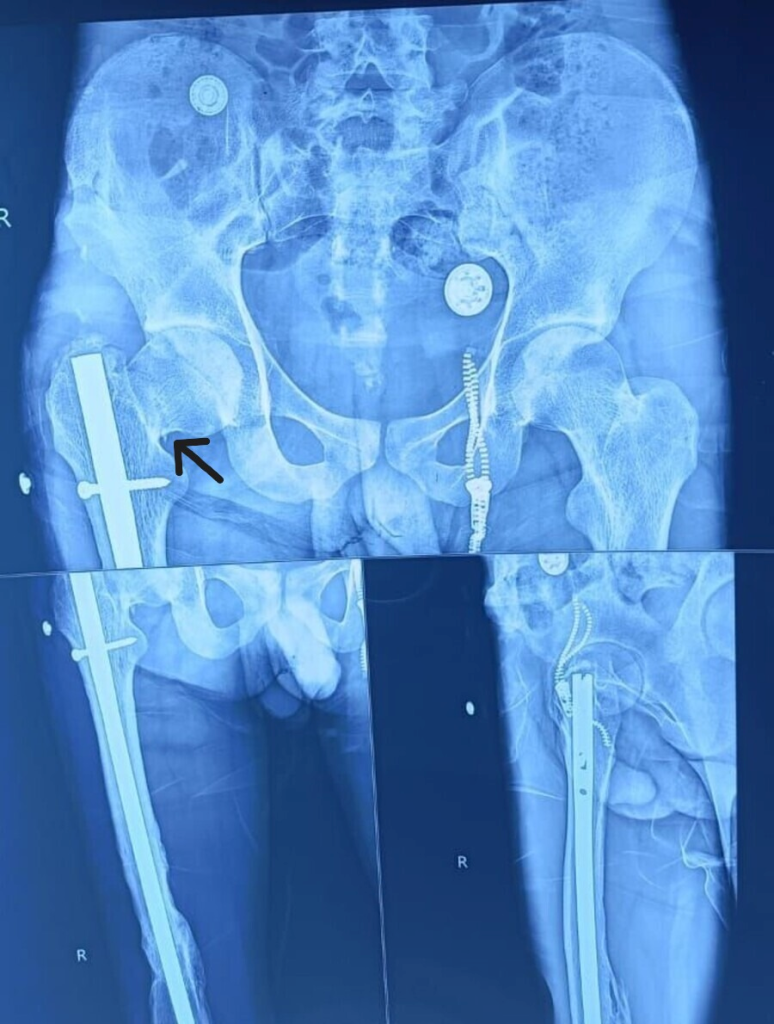

The patient presented to us with complaints of pain and being unable to bear weight on his right lower limb. On examination, the right lower limb was found to be in flexion, abduction, and external rotation. There was a healed scar mark on the lateral aspect of the thigh. X-ray showed the neck of the femur fracture, which is marked with an arrow in the anteroposterior (AP) and lateral images, which is undisplaced as shown in (Fig. 1a-c), Garden classification type 2. As the patient is young, there is no sign of osteoporosis or sign of decreased bone density on X-ray.

Figure 1: Pre-operative image neck of femur fracture with the femur interlocking implant in situ in anteroposterior (AP) (a and b) and lateral images (c), arrow showing undisplaced neck of femur in both AP and lateral image.